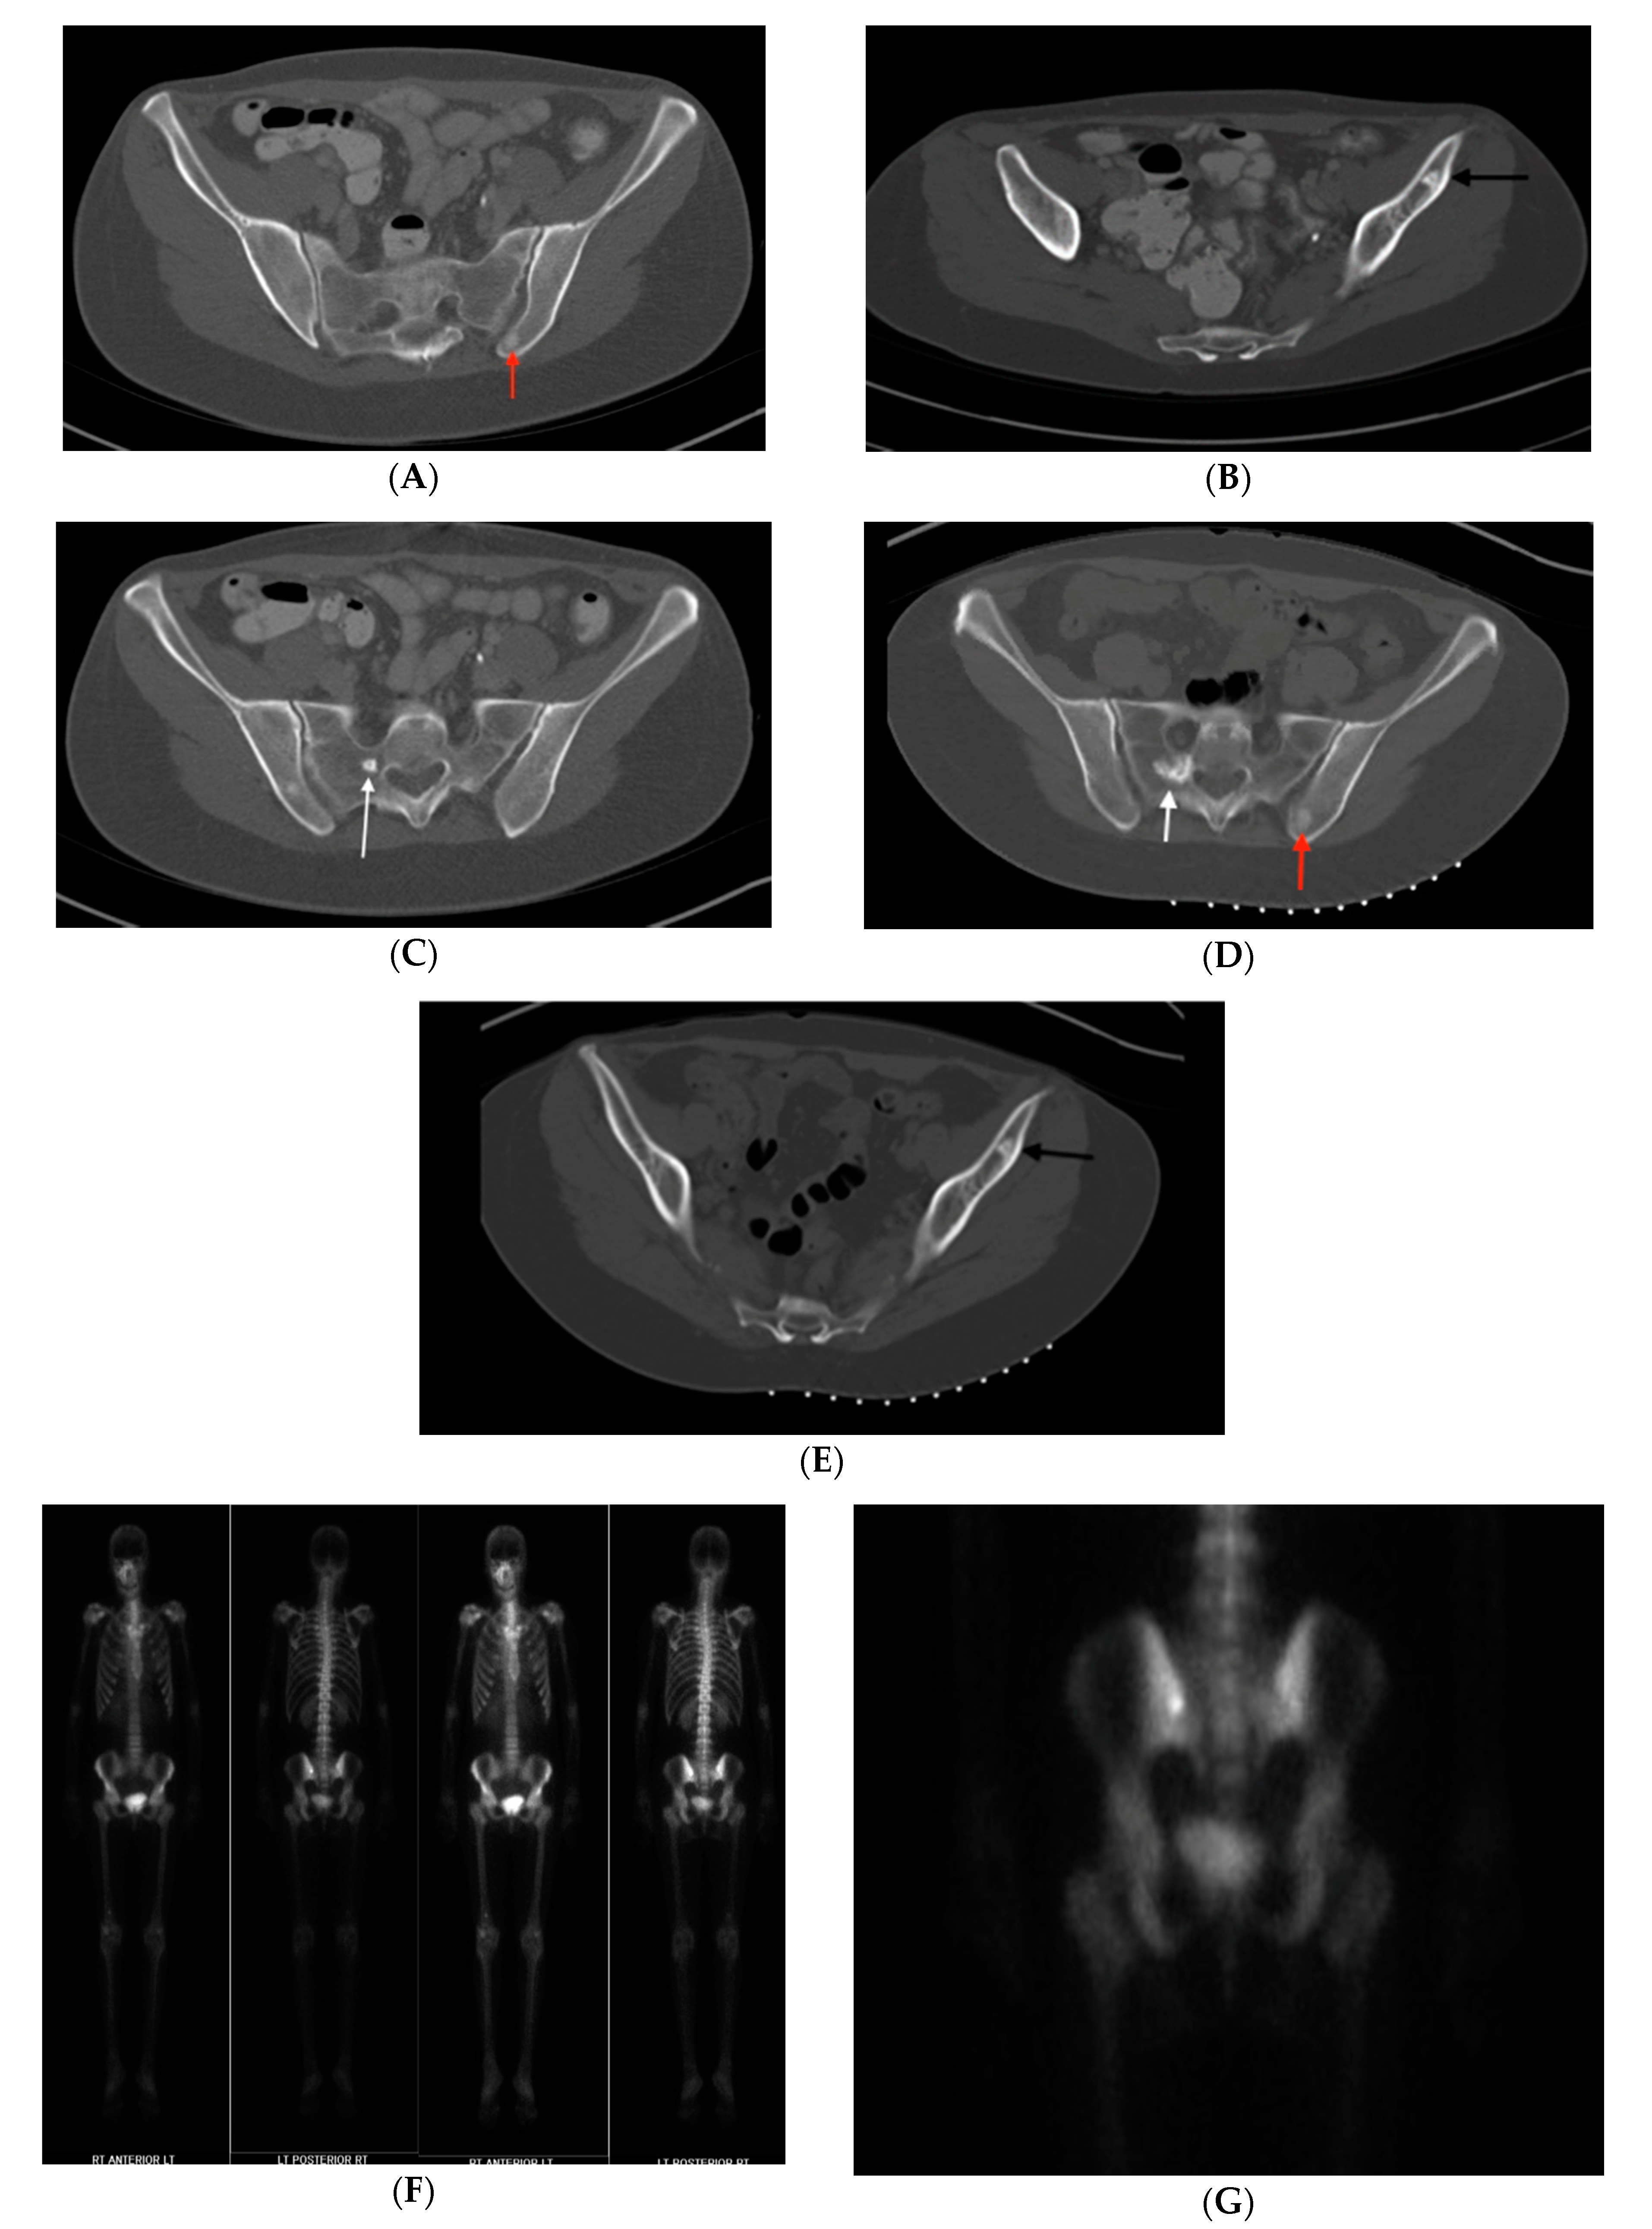

Figure 3. (AC) Case 1. Pelvic axial CT shows an enlarged lesion 5 years after original discovery, (A) Initial CT displays a 16 mm sclerotic focus in the left posterior acetabulum. (B) Repeat CT demonstrates growth of the bone lesion to 21 mm, central radiodensity and peripheral “rose thorn” appearance. (C) Higher magnification emphasizes characteristic features. Despite its enlargement, it was felt to be otherwise typical for BI, so observation was recommended.